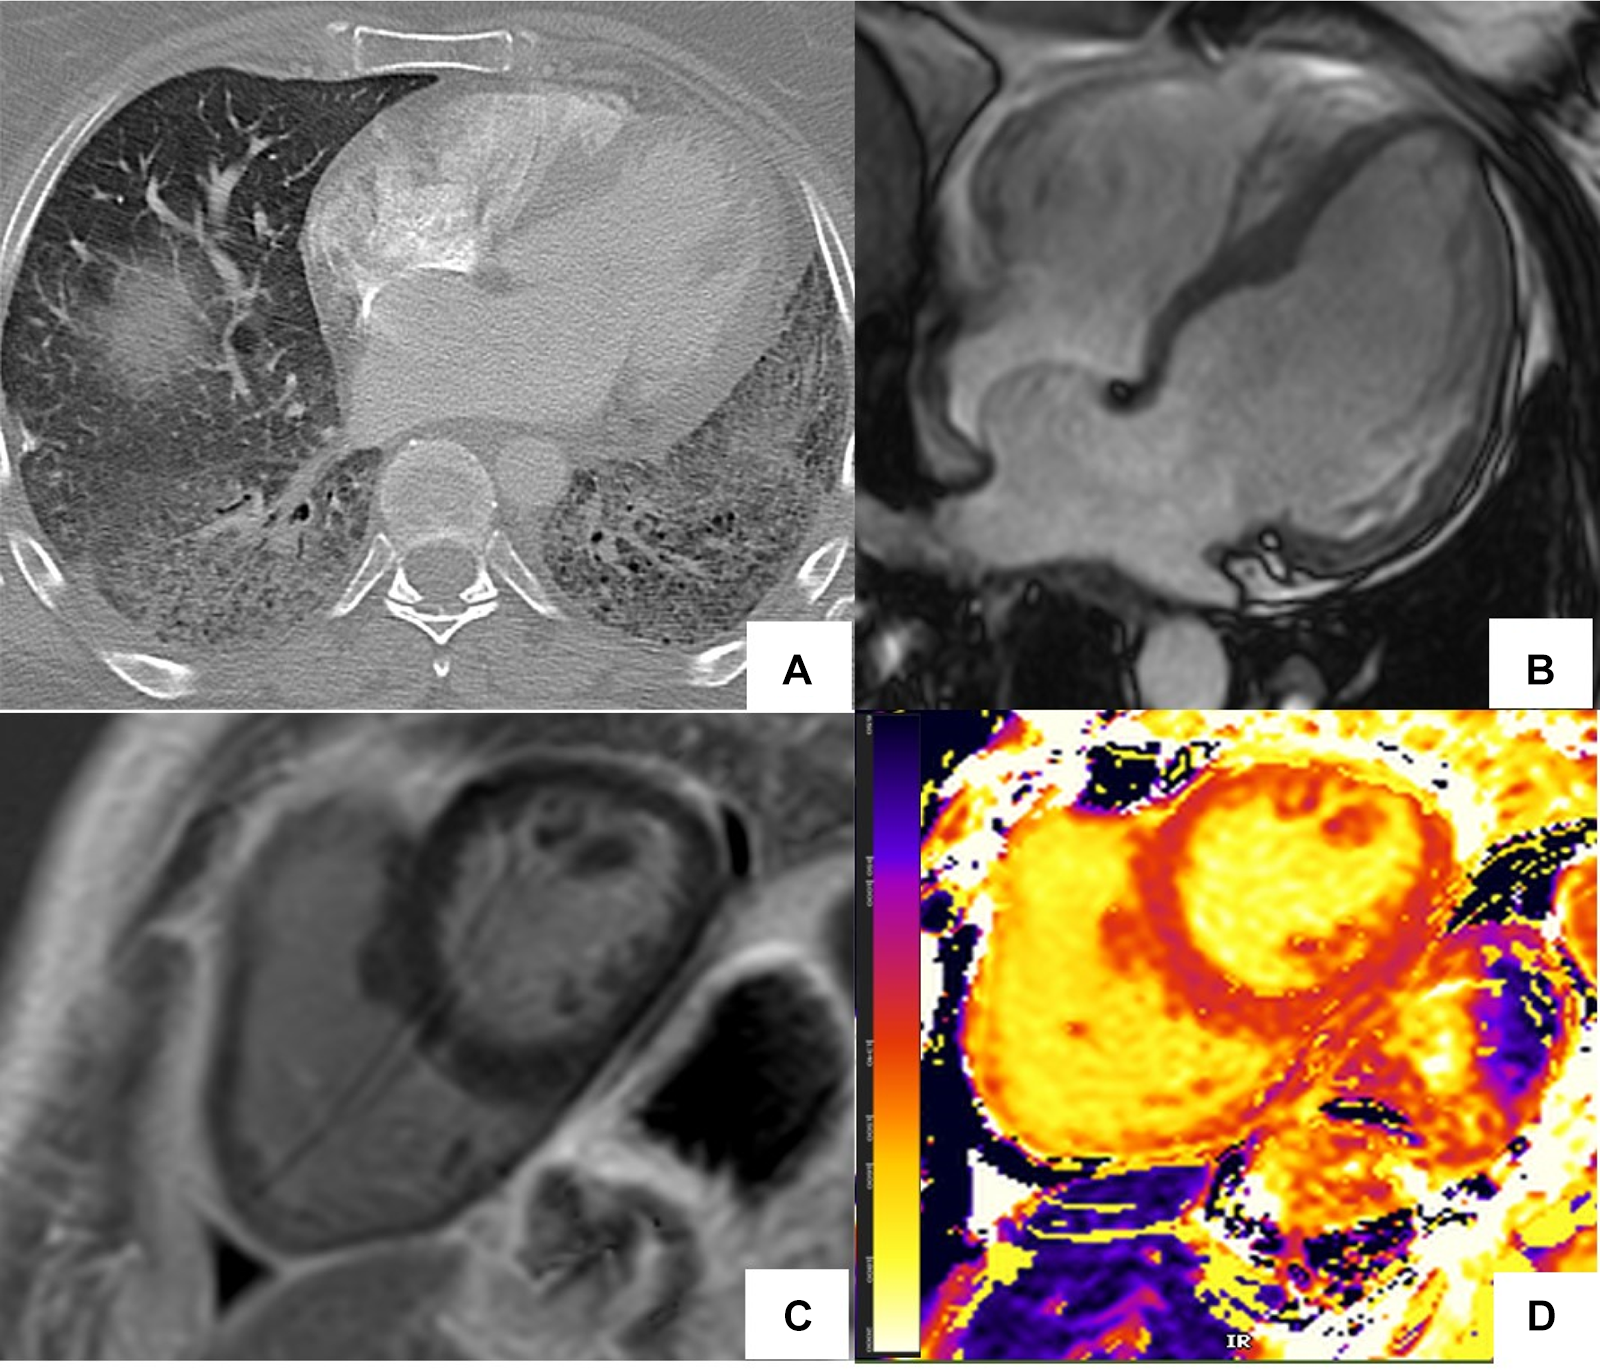

Figure 5

Abnormal cardiac MR (CMR) T1 mapping in subclinical myocardial inflammation in a patient with scleroderma. 37-year-old female with scleroderma-related interstitial lung disease (A Chest CT) and increasing dyspnea on exertion. 1.5 T cine CMR had a normal LV ejection fraction of 59% and no regional wall motion abnormality. 4ch cine showed flattening of the inter-ventricular septum consistent with known pulmonary hypertension (B) On short-axis late gadolinium enhancement phase-sensitive inversion recovery (LGE-PSIR) there was no myocardial late gadolinium enhancement, only trace pericardial effusion (C) Native T1 values were elevated to 1,250 ms on the native T1 color map (D) suggesting active myocardial inflammation.